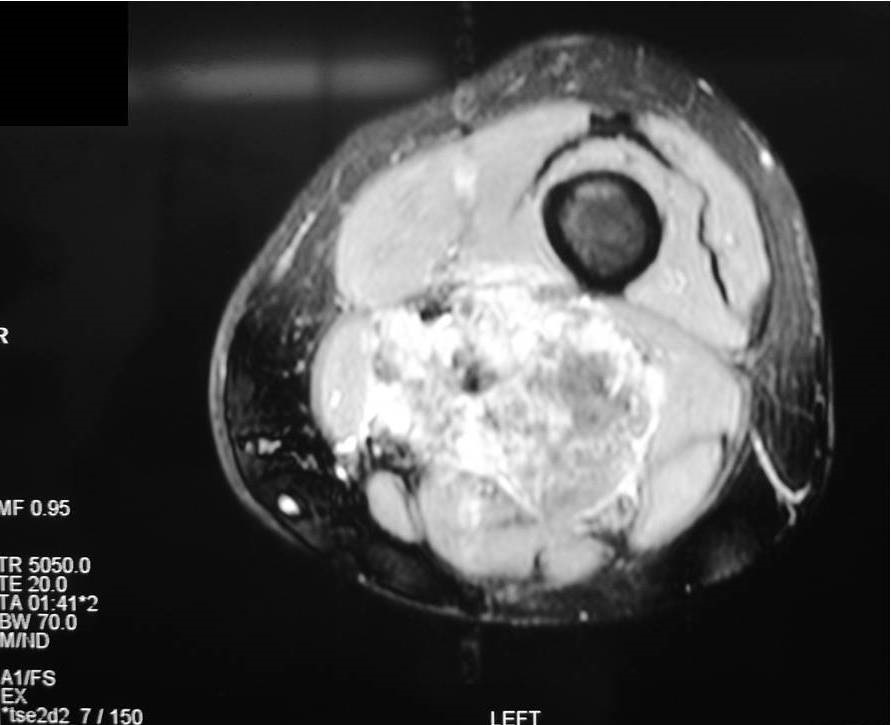

On radiographs, extraskeletal osteosarcomas show a mass with soft tissue density and variable amounts of mineralization best visualize on an Xray or CT scan, which may appear as a dense, cloudlike area (Fig. 1-3). A well circumscribe heterogeneous mass, Isointense to muscle on T1-weighted images and isointense to mildly hyperintense on T2-weighted images (Fig. 4-7). Mineralized areas will be dark on T1 and T2 weighted images.

Fig. 6 & 7: MRI of an Extraskeletal Osteosarcoma Axial T2 –weighted fat-suppressed image shows a heterogeneous and hyperintense signal in the posterior compartment of the thigh, central hypointense areas concordant with necrosis and mineralization. Axial T2- weighted fat suppress contrast enhanced image (Fig. 7) demonstrates an enhancement area in the posterior compartment of the thigh.